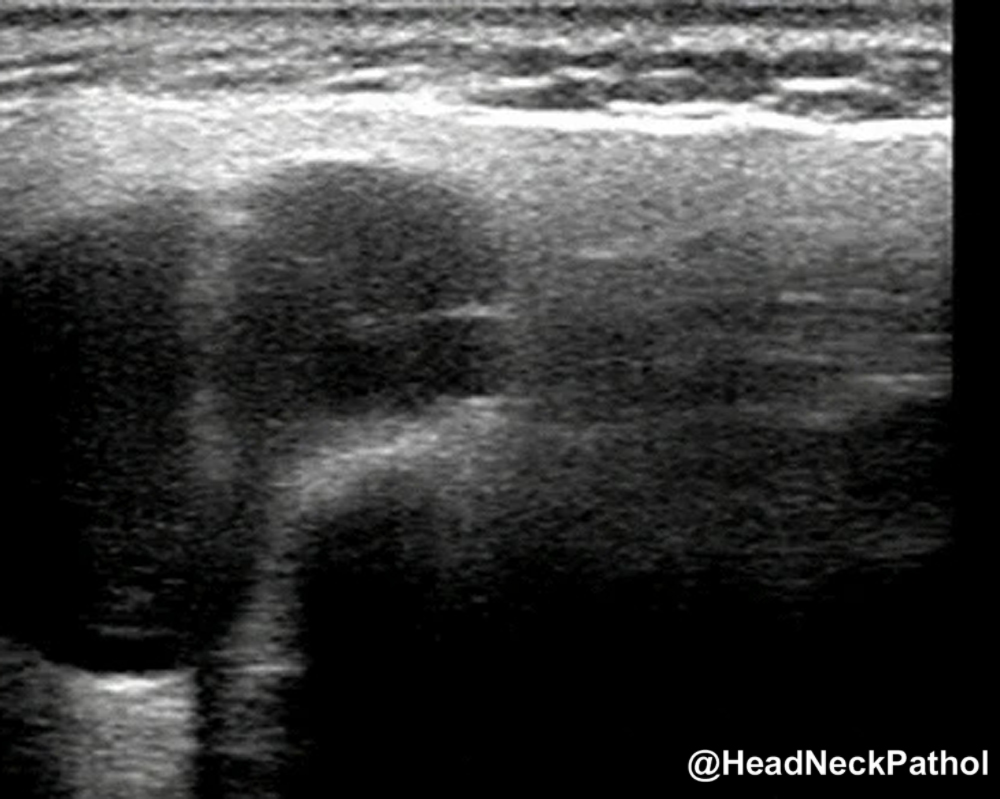

Characterization of CD8 + & CD68 + Microenvironment & PDL1 Expression in HPV-related Multiphenotypic Sinonasal Carcinoma

Silva de Araújo, Gonçalves de Paiva, Lima Fernandes, et al.